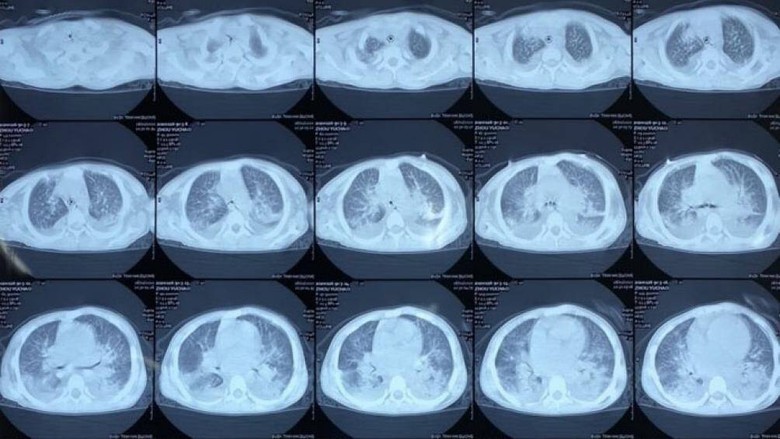

Hình ảnh chụp phổi của bệnh nhân

Trước đó, tối 26/1, Bệnh viện đa khoa tỉnh Hải Dương tiếp nhận bé Zhou Yuchao (10 tuổi, quê ở tỉnh Hồ Nam, Trung Quốc) được chuyển đến từ Trung tâm Y tế huyện Gia Lộc trong tình trạng khó thở, niêm mạc nhợt nhạt, da tím tái, không sốt. Qua chẩn đoán hình ảnh, hội chẩn, bệnh nhân được kết luận suy hô hấp, viêm phổi, có tiền sử suy thượng thận bẩm sinh, chưa loại trừ khả năng bị phù phổi.